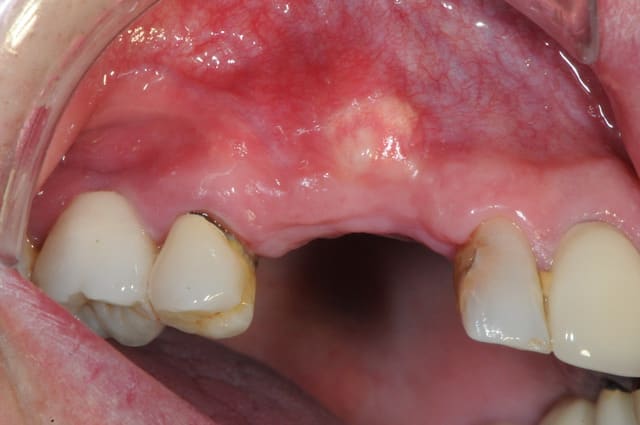

la suite après 4 mois de cicatrisation